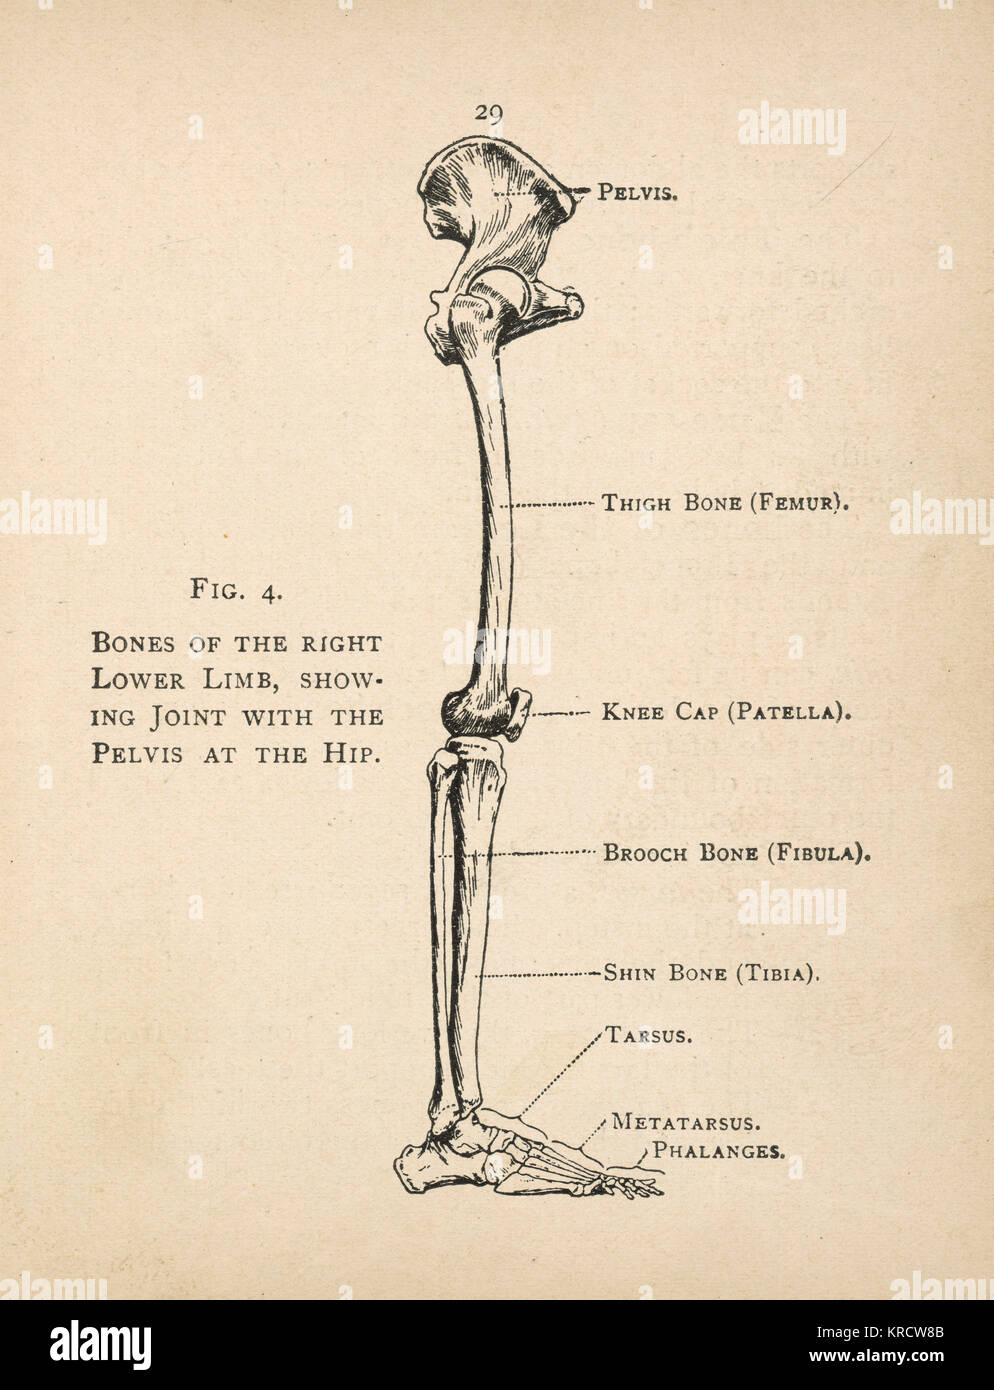

RMKRCW8B–Diagramme de l'os de la jambe droite, montrant l'articulation avec le bassin de la hanche. Date : 1908